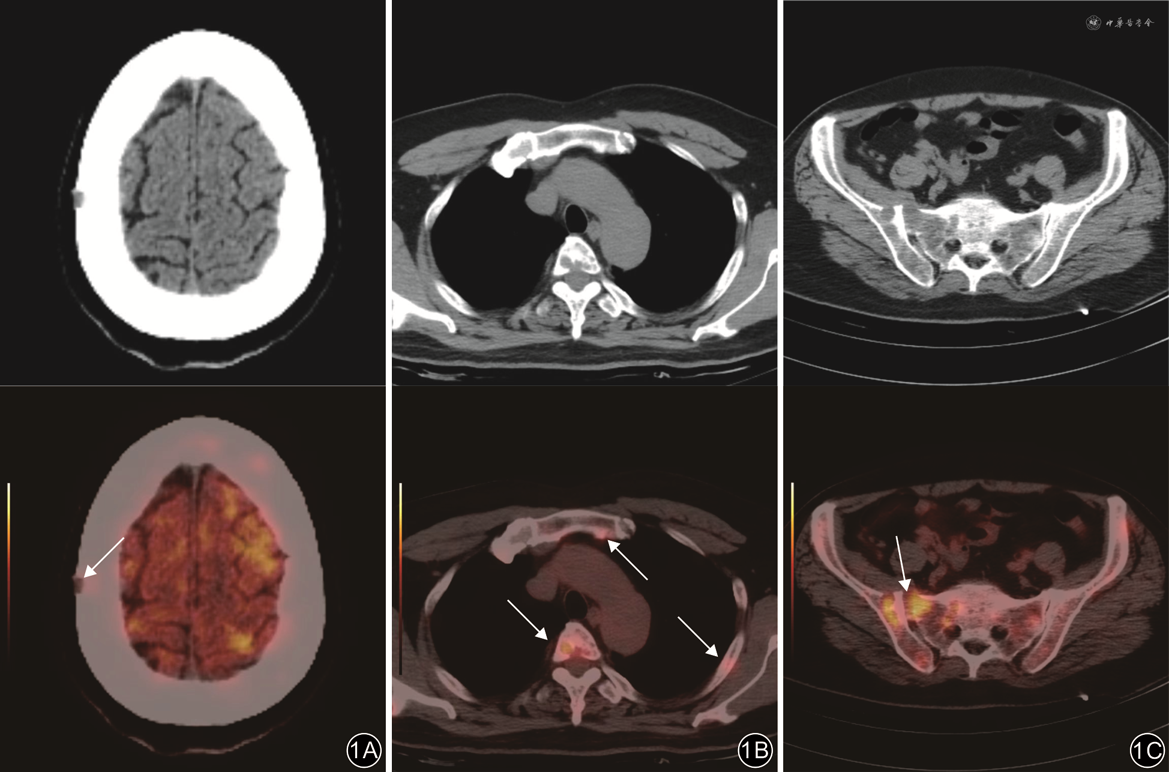

肺癌骨转移和前列腺癌骨转移病灶以高代谢为主,SUVmax较高,分别为5.70~29.10(15.51±5.60)和4.30~15.10(9.41±3.47)。在42例肺癌骨转移病例中,有41例(97.6%)显示SUVmax≥6.0;而在30例前列腺癌骨转移病例中,有24例(80.0%)显示SUVmax≥6.0。MM病灶以弥漫性轻中度代谢为主,SUVmax较低,为0.80~12.00(5.39±2.84)。在36例MM病灶中,有12例(33.3%)显示SUVmax≥6.0。3组间SUVmax比较差异有统计学意义(F=54.66,P<0.001),组间两两比较差异均有统计学意义(P值均<0.05)。

注:上排为CT图像;下排为对应位置的正电子发射体层摄影(PET)/CT融合图像